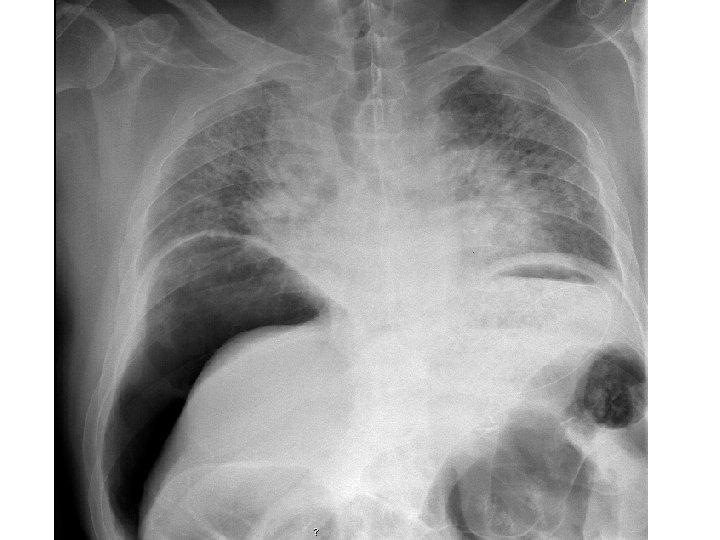

5 - Falso ventre agudo (causas não cirúrgicas) Doença cardíaca – enfarte do miocárdio, pericardite. Doença pulmonar – pneumonia, enfarte pulmonar. Doença endócrina – diabetes com ceto-acidose, insuficiência supra-renal aguda. Doença metabólica – insuf. renal, porfiria, febre mediterránica familiar (escaro-nodular), hiperlipidémia. Doença neurogénica – Herpes zooster, neurosífilis (tabes dorsalis), compressão radicular. Doença génito-urinária – pielonefrite, cólica renal, salpingite aguda, torção testicular. Doença hematológica – anemia de células falciformes. Doença gastro-intestinal – hepatite aguda, gastroenterite, pancreatite.

Ventre agudo: exames imagiológicos Rx simples do abdómen e Rx abdominal de pé; Rx do tórax Pneumoperitoneu; Rx tórax em decúbito lateral esq. (impossibilidade de exame de pé) Litíase calcificada da vesícula (10%) e renal (90%) Oclusão: distensão de ansas e níveis. Íleos paralítico Ecografia abdominal e pélvica (patologia vesicular e vias biliares, pancreática, apendicular, renal, útero e anexos, aneurismas, derrame peritoneal) TAC abdominal: gás e sangue intraperitoneal, pancreatite, diverticulite, trombose da mesentérica, peritonite avançada.